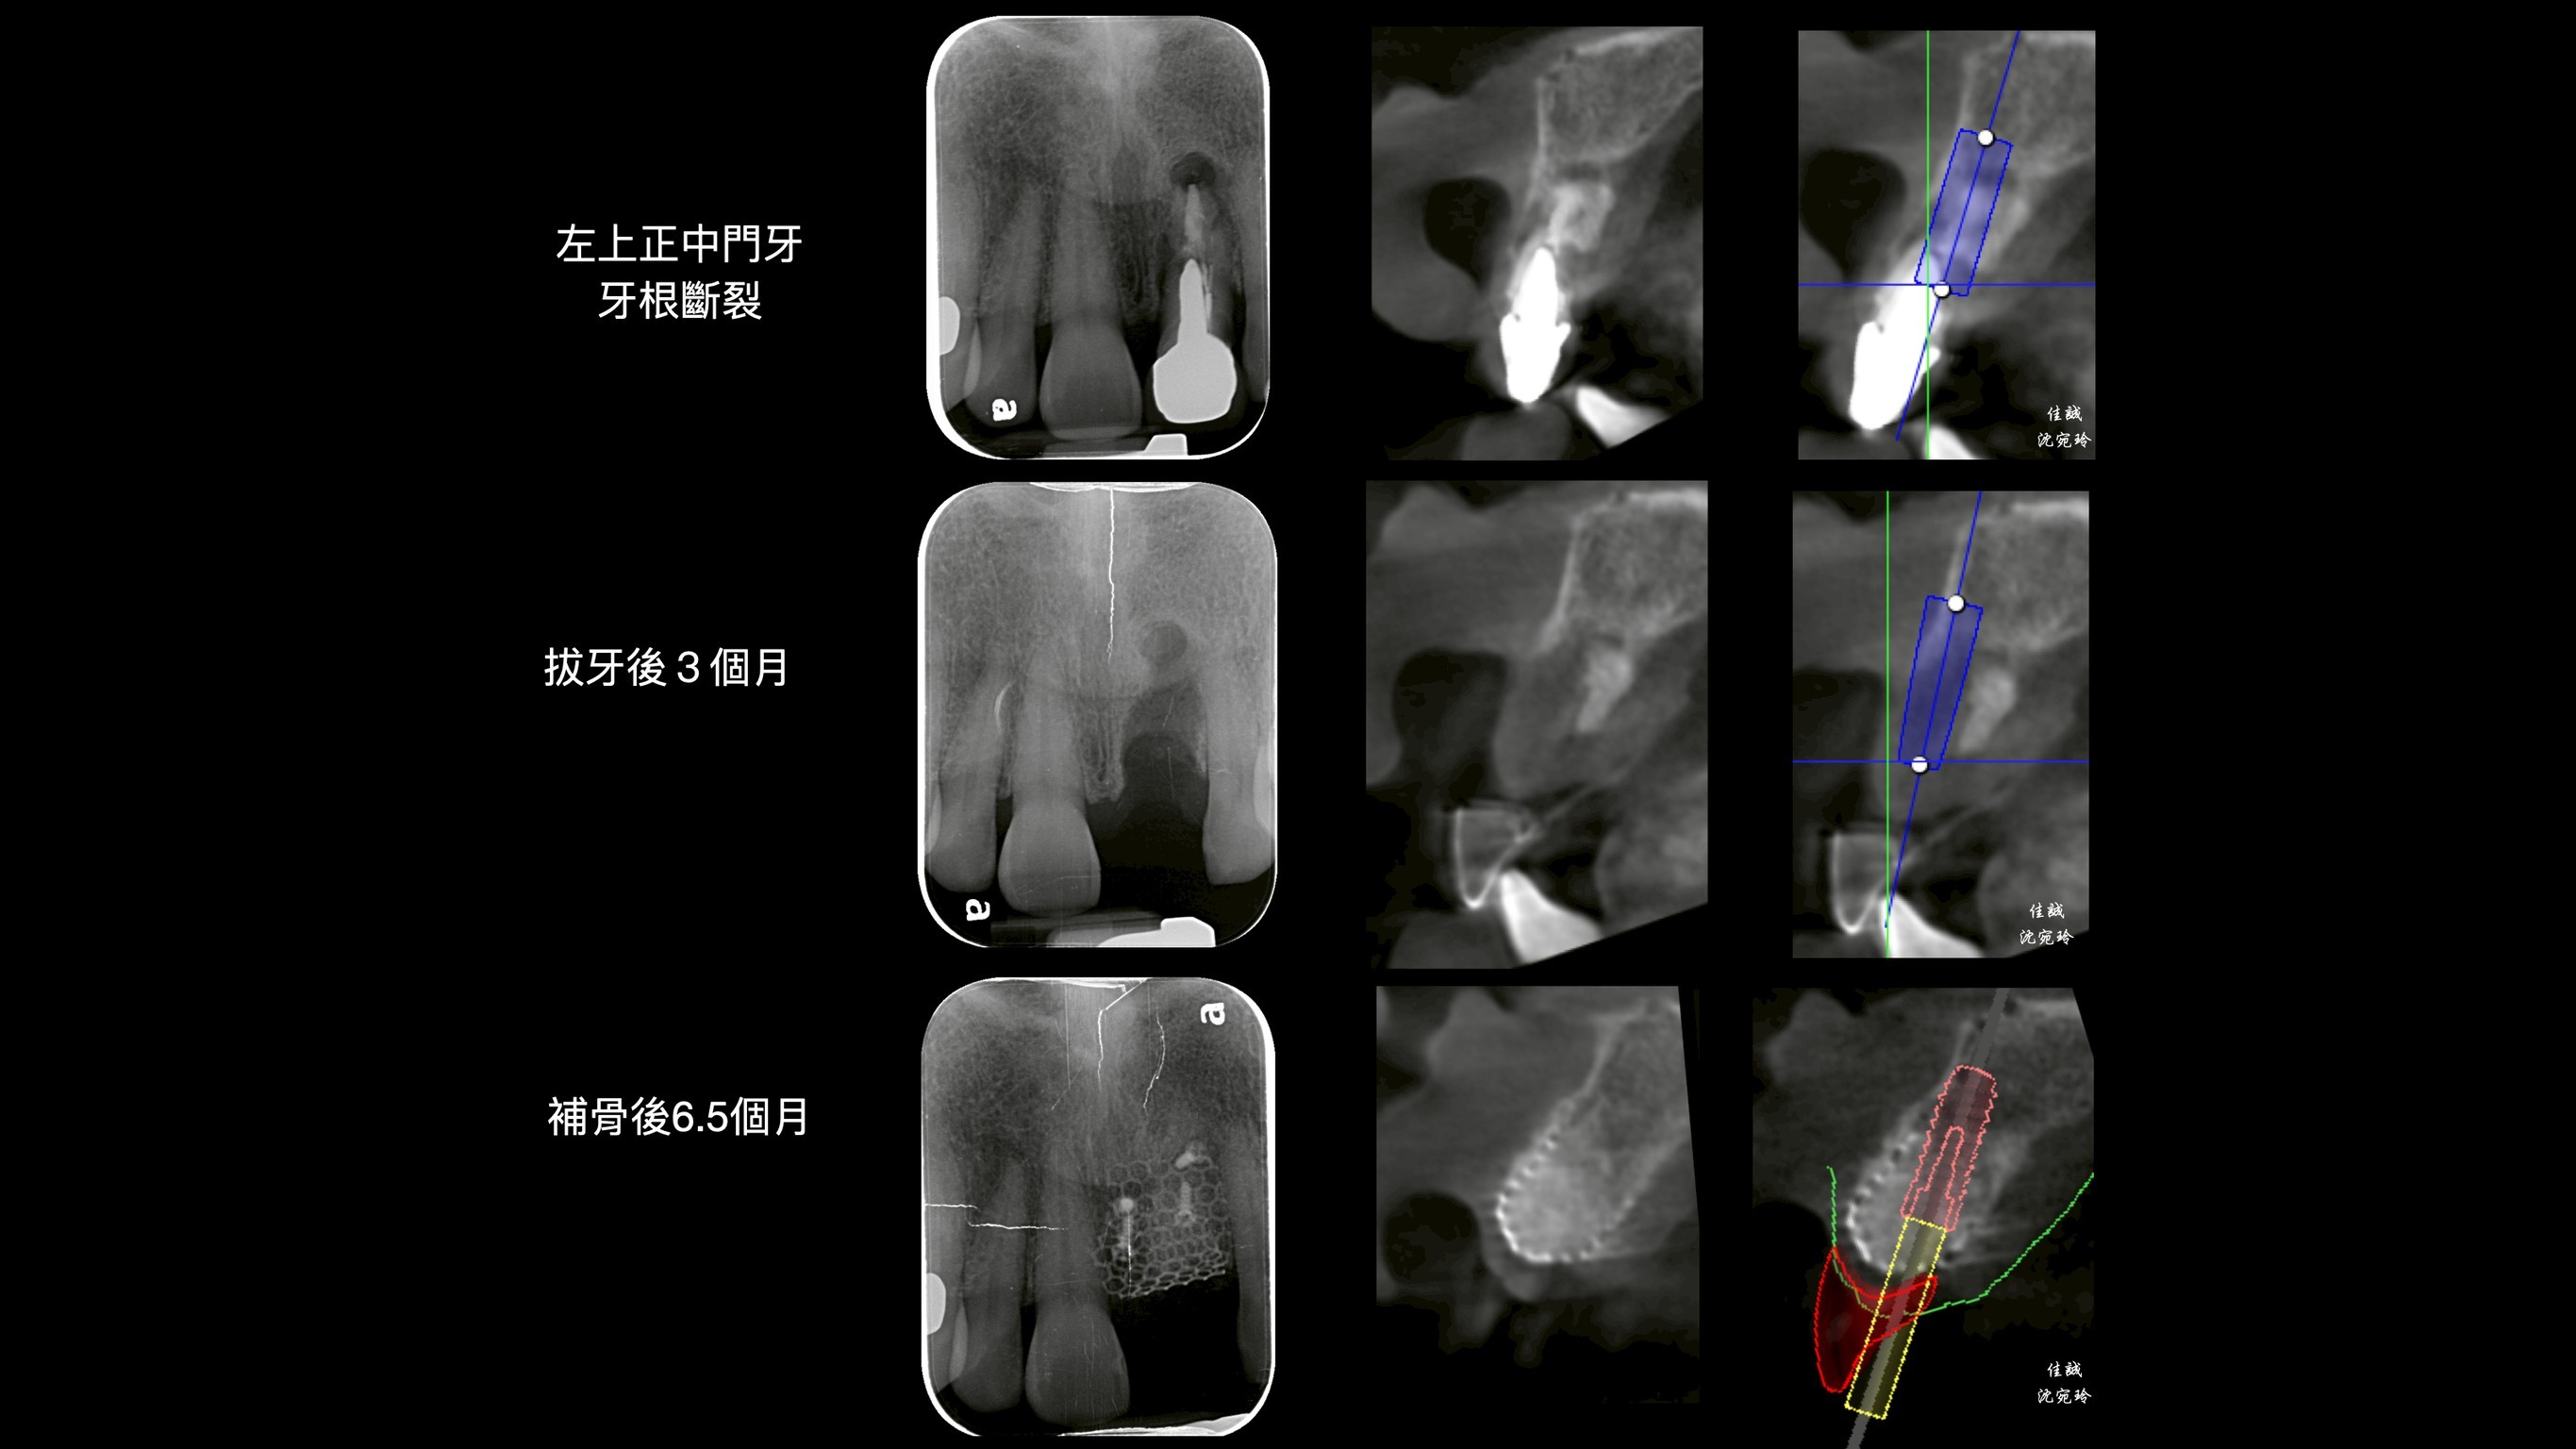

C小姐經其他醫師轉診,因上顎門牙牙根斷裂,感染而造成膿腫,在頰側、顎側、垂直高度皆有嚴重骨缺損。因此在補骨手術中,醫師選擇使用高難度的鈦網合併適度皮瓣減張,可以有效率的達到接近理想的成果。

其中,不論從診斷、補骨手術前及植牙的手術導板規劃階段,我們都會先把植體和其假牙相對位置找出來,來制定接下來的治療計劃。